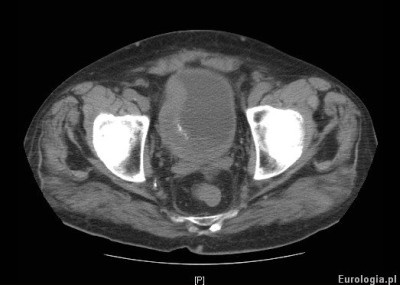

Fot. Tomografia komputerowa - guz pęcherza moczowego